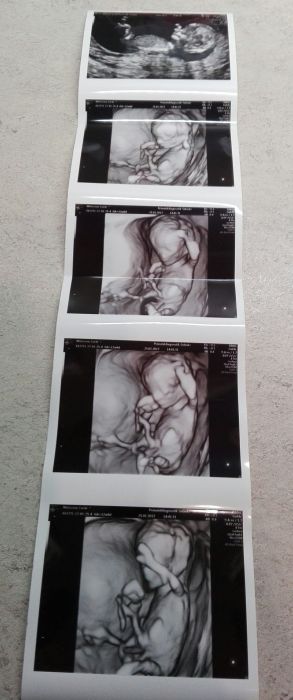

Tak já mám po screeningu - negativní. Podle pana doktora "nejsem nositelkou geneticky poškozeného plodu"

Takže zatim má všechno co má mít. Ptal se, jestli je pro nás důležitý co to bude, tak jsme řekli, jestli to uvidí, že to může říct. Dloooouho se ho snažil nějak natočit, ale ten malej pacholek si dal zrovna nohy křížem a už se ani nehnul, takže nevíme

Tak prej snad ve 20.týdnu, až k němu pojedeme na 2.utz. Vytiskl nám nějaké fotky, tak zkusím vložit. Ještě nám dal na flešku pár krátkejch videí. Má dokonce 4D ultrazvuk prej.